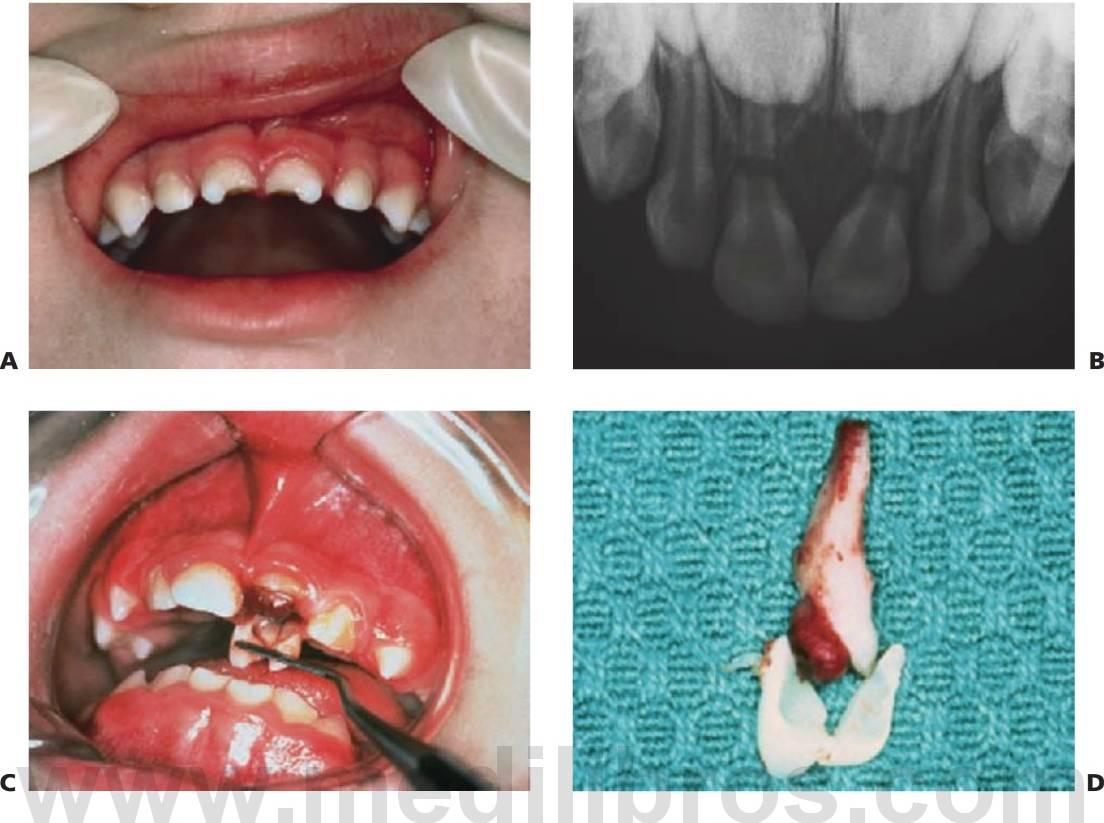

Defectos de desarrollo del esmalte

Además del daño causado por el desplazamiento de los dientes temporales dentro de las criptas de los sucesores permanentes (v. Secuelas de los traumatismos de los dientes temporales más adelante en este capítulo), pueden verse dañados los dientes no erupcionados que se encuentran en la línea de las fracturas de la mandíbula. Los defectos pueden incluir:

- Hipoplasia o hipomineralización del esmalte.

- Dislaceración de la corona y las raíces.

- Desplazamiento del diente en desarrollo dentro del hueso.

- Detención del desarrollo del diente, con obliteración del conducto pulpar.

- Hipoplasia (fig. 7.18E) o hipomineralización (fig. 7.18B) de dientes sucedáneos.

- La dislaceración de la corona o la raíz varía según el estadio de desarrollo (fig. 7.18C, D).